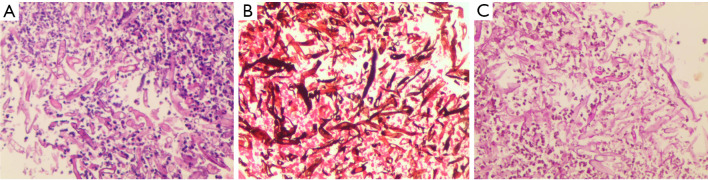

Case description: A 39-year-old male patient was diagnosed with PM and complicated by bronchial obstruction. Although surgical debridement of mucormycosis and antifungal therapy are generally preferred treatment, our patient presented with a high burden of invasive disease and was deemed ineligible for surgery. We therefore had to compromise and palliate his bronchial obstruction with a bronchial stent while continuing intravenous, nebulized, and bronchoscopically applied antifungals. The intervention markedly alleviated the patient's symptoms of chest tightness and dyspnea. However, given the advanced stage at presentation, the prognosis was already poor. Despite these measures, the aggressive underlying infection continued to progress, ultimately leading to erosion into a major vessel and catastrophic hemoptysis.

Conclusions: The implantation of bronchial stents in patients with PM can effectively alleviate severe bronchial obstruction caused by mucormycosis infection, improve pus drainage, and promote infection resolution. However, as a complete surgical resection of the lesion was not performed, the patient remains at risk of potentially catastrophic hemoptysis due to the possibility of pulmonary vascular invasion by mucormycosis. The potential increase in hemoptysis risk associated with stent implantation warrants further investigation.